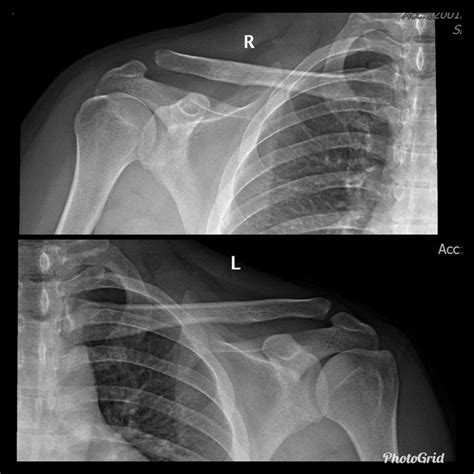

• AC Joint Separation: This occurs when the ligaments supporting the AC joint are torn, often due to a fall or direct impact. It is graded on a scale from I to VI, with higher grades indicating more severe injuries.

• Joint Space: The space between the clavicle and scapula should be uniform. Any narrowing or widening can indicate injury or degeneration.

• Bone Alignment: The bones should be properly aligned. Any displacement or misalignment can suggest a fracture or dislocation.